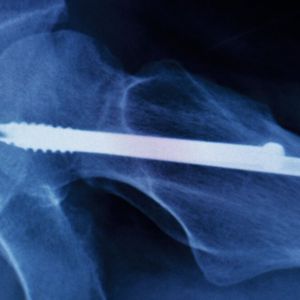

Wer sich schon einmal Schulter, Knöchel oder Handgelenk kompliziert gebrochen hat – beispielsweise bei einem Sturz mit dem Fahrrad – der weiß die Erfindung medizinischer Implantate zu schätzen. Geben sie doch dem lädierten Knochen wieder Stabilität und ermöglichen so erst die Heilung. Manche Implantate verbleiben dauerhaft im Körper, andere werden nach Abschluss des Heilungsprozesses wieder entfernt.

Letzteres macht eine zweite Operation notwendig. Jede OP ist für den Patienten jedoch ein potenzielles Risiko, weshalb – wo möglich – verstärkt auf solche Implantate gesetzt wird, die sich im Körper nach definierter Zeit von selbst wieder abbauen. Allen Implantaten gemein ist: Eine Verkeimung stellt für den Patienten eine große Gefahr dar und muss zwingend vermieden werden. Über den Einsatz bestimmter Werkstoffe kann eine intrinsische Infektionsprophylaxe betrieben werden, doch müssen natürlich auch alle anderen Materialeigenschaften im Sinne der medizinischen Anwendung stimmen.